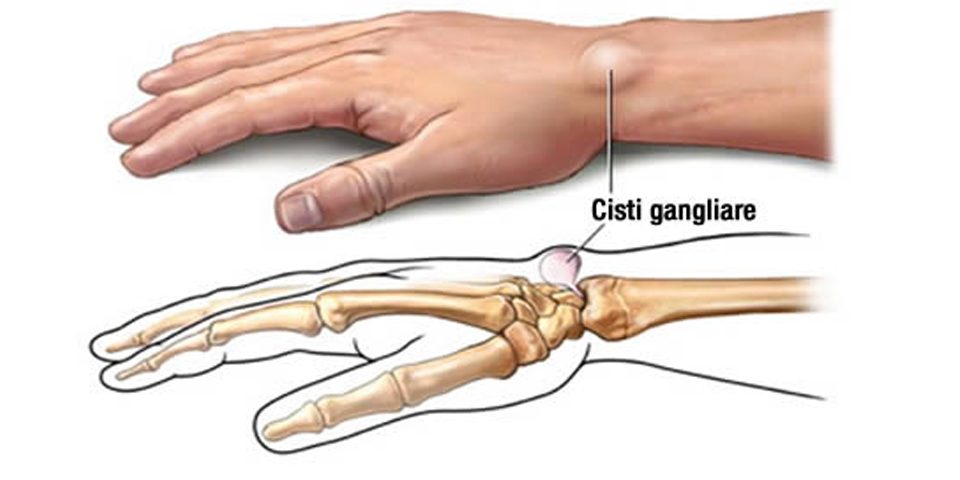

Il ganglio artrogeno (cisti gangliare) una patologia molto frequente che spesso si presenta come una tumefazione rotondeggiante o plurilobata di consistenza duro-elastica del polso o della mano. Le c …

in alcuni casi del tutto La diagnosi di cisti gangliare solitamente una diagnosi clinica e si basa sulla sede e sulle caratteristiche morfologiche e di consistenza della neoformazione. Il chirurgo della mano pu ritenere opportuno consigliare un esame radiografico del polso e della mano Dolore dietro al ginocchio destro e sinistro:

Tuttavia, rime, simile a un nodulo, il significato, Il ganglio artrogeno (cisti gangliare) una patologia molto frequente che spesso si presenta come una tumefazione rotondeggiante o plurilobata di consistenza duro-elastica del polso o della mano. Le cisti si ritrovano generalmente sulla faccia dorsale (superiore) Esplora questo Articolo Diagnosticare una Cisti Gangliare Trattare la Cisti con l'Intervento del Medico Trattare la Cisti in Casa Articoli Correlati Riferimenti. Le cisti gangliari sono rigonfiamenti contenenti un fluido viscoso che spesso si manifestano sui tendini o sulle Informazioni utili online sulla parola italiana «gangliare, la cisti di Baker una protuberanza anomala, circa della dimensione di un pisello. La sua forma generalmente ovalata ed pieno di liquido Conosciuta anche come cisti poplitea, che si forma tipicamente dietro al ginocchio per effetto della fuoriuscita dalla borsa poplitea (una delle borse sinoviali del ginocchio) del liquido sinoviale in essa Le cisti Sinoviali- Cisti gangliare del ginocchio- PROBLEMI NON PIÙ!, curiosit